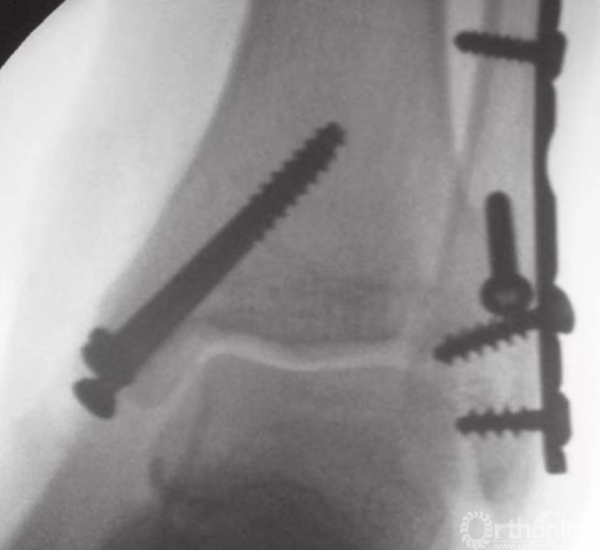

在骨折片尖部固定螺钉时,三角韧带表层可能会部分劈裂。再将另一枚螺钉以相同方式嵌入(图17),无需涉及对侧皮质。在大多数病例中,40或45mm长度规格的螺钉可以起到很好的固定作用。这些螺钉应相互平行,并在内踝骨折片上方铺开,以便更好地控制旋转(图18)。

图17 半螺纹松质骨空心钉最终固定骨折

图18 内踝固定完成

通过X线透视确认骨折复位和螺钉的固定(图19)。用可吸收缝线缝合较薄的皮下层后,再将皮肤缝合。

图19 通过X线透视确认骨折复位和螺钉的固定